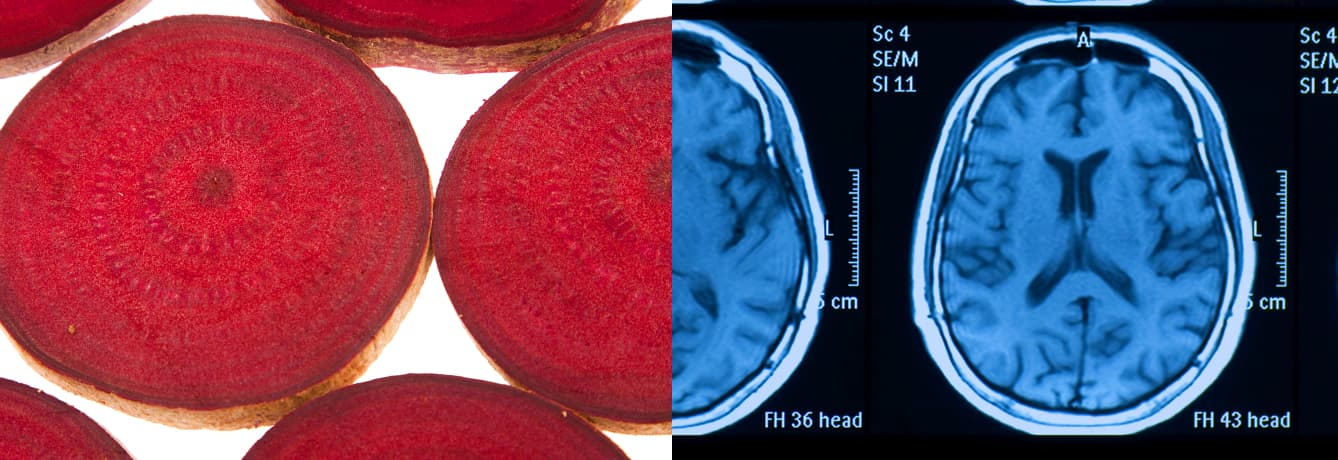

Want to give yourself better odds of remaining sharp in later years? Add some beets to your anti-Alzheimer’s arsenal. New research suggests beets could help increase blood flow to the brain .

Researchers from Wake Forest University had 14 seniors (70 years old and up) drink either 16 oz. of beet juice or eat a control diet in the morning for two days, then used MRI machines to measure blood flow to the brain. The groups switched diets for another two days, then were tested again. The result: The beet-juice drinkers enjoyed 21% increased blood flow to the frontal lobes — sensitive areas of the brain vulnerable to the degeneration that leads to dementia. “I think these results are consistent and encouraging — that good diet consisting of a lot of fruit and vegetables can contribute to overall health,” said Gary Miller, Ph.D., a senior investigator on the project.